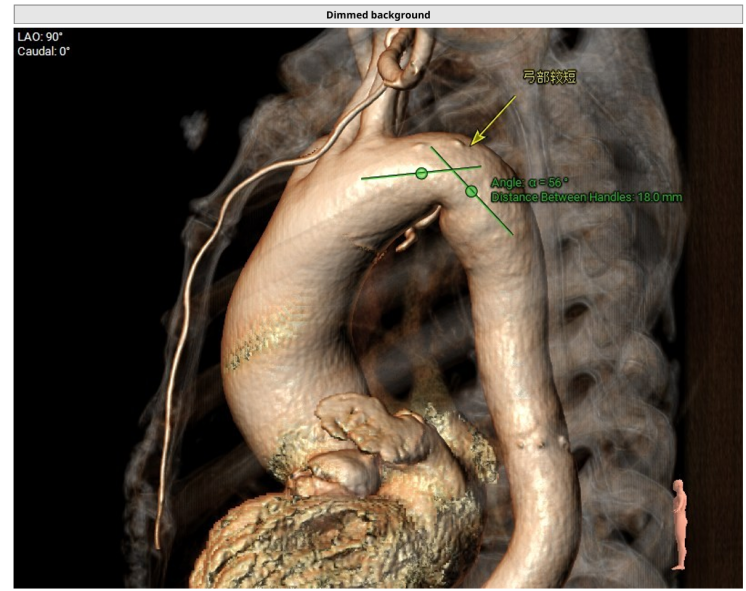

更棘手的是,王奶奶的主动脉弓部像打了个 「急转弯」,血管又短又弯,加上她本身心室小,又有冠心病、高血压,传统开胸换瓣手术风险极高,就像在 「钢丝上跳舞」。

手术使用目前最先进的「球扩瓣」 瓣膜,瓣膜小、容易过弯,具有优秀的输送性及释放稳定性,能很好地在王奶奶的「急转通道」里安全穿梭。

最关键的一步是输送瓣膜过弓。王奶奶的主动脉弓严重弯曲,团队凭借精湛的技术,让装载着瓣膜的输送系统顺利 「过弯」 并跨瓣。瓣膜定位后,医生精准释放了 23 mm 的人工瓣膜,在正确的位置安装好了新的 「心门」。